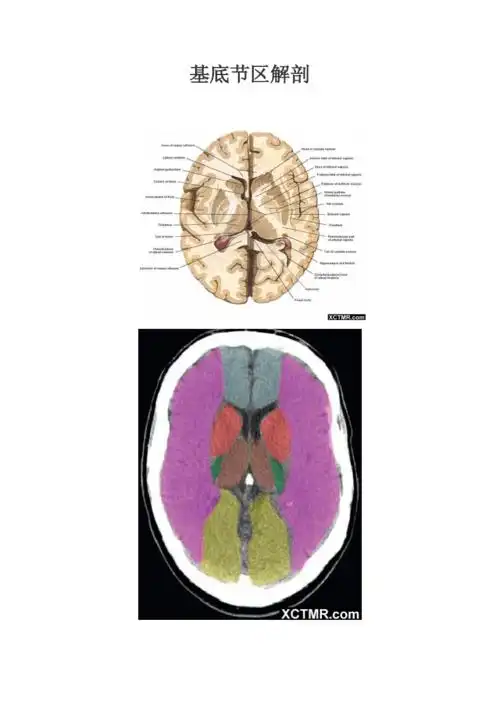

神级系统解剖端脑基底神经节

基底节对称性病变的病因和影像学特征影像天地

内囊丘脑基底节区解剖与定位二

【影像基础】值得收藏的基底节及周围区域解剖详图

基底节区层面颅脑ct断层解剖

基底核与基底节区解剖与定位

基底节区解剖位置关系图及临床ppt参考课件ppt

"基底节区"的准确定义是什么?求助!